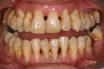

An infectious disease that presents with inflammation within the supporting tissues of the teeth. Progressive attachment and bone loss are accompanied by pocket formation and/or recession of the gingiva. Chronic periodontitis is the most frequently occurring form of periodontitis. It is found most often in adults but can also occur in young patients. Plaque and calculus accompany chronic periodontitis. The sequence of attachment loss is typically slow; however, periods of fast development may occur. The microbial configuration is not consistent or predictable.

Periodontitis in which there is gradual and persistent evidence of periodontal pocket formation, injury to the ligamentous attachments of the teeth, alveolar bone destruction, and eventually, dental loosening.